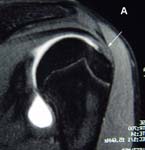

An experienced physician, therapist, shoulder surgeon, or sports medicine surgeon can usually recognize the signs of rotator cuff problems. While the rotator cuff can not be directly visualized on X-rays, there may be subtle signs on the bones of the shoulder joint that can suggest a problem. If suspected, the diagnosis can almost always be made or confirmed using Magnetic Resonance Imaging techniques (MRI). However, many different problems can present with shoulder pain, so a thorough clinical examination by an experienced orthopedic shoulder surgeon is recommended. (See Fig. 3.)

The physical examination and history are a reliable means to diagnose rotator cuff weakness and pain. Many times, persons will have no abnormalities on X-ray (the cuff can not be visualized with x-ray), but MRI is very reliable in confirming a suspected diagnosis. Frequently, and MRI arthrogram will be performed. For this study, a contrast ‘dye’ is injected into the joint just prior to the MRI. This study is nearly 100% accurate in diagnosing a tear. (See Fig. 3)

X-rays may show bony injuries reactions to a dysfunctional rotator cuff tear. Cysts can occasionally be visualized in the region of the cuff insertion at the humerus, the humeral head may migrate toward acromial roof, or bone spurs may develop on the undersurface of this roof. MRI images give cross-sectional pictures of the rotator cuff. Small tears or fraying of the cuff tissue are frequently seen and large and massive tears are easily apprecitated.